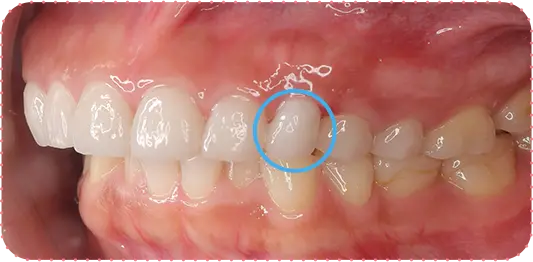

Before

After

主訴

前歯をきれいにしたい

治療期間

8か月

治療費

40万円

治療内容

右上2番をマウスピース矯正で移動してラミネートべニアにて修復

治療のリスク

【マウスピース】

矯正装置を初めて装着した時は、違和感や圧迫感、疼痛などを感じる場合があります。

歯根吸収や歯肉の退縮が起こる場合があります。

1日の装着時間が長いため、口内清掃不足だとむし歯・歯周病のリスクが高くなります。

歯の移動後に保定装置(リテーナー)の使用が不十分の際は、後戻りが生じる場合があります。

マウスピースの装着時間が少ないと治療期間が長引く場合があります。

【セラミック】

咬み合わせによっては、セラミックが欠ける可能性があります。